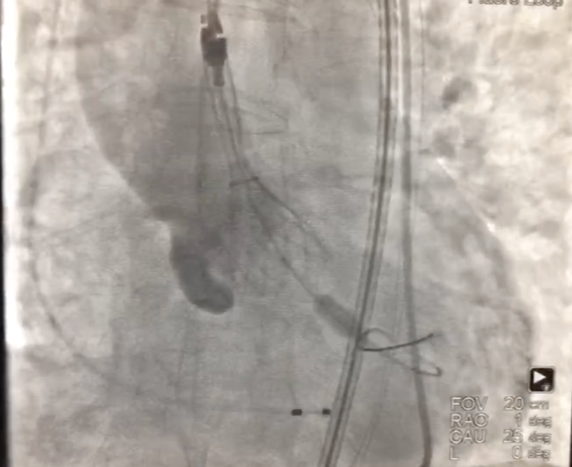

2、经左股动脉入路,顺利跨瓣后,选取20 mm球囊于180 bpm下快速起搏预扩,显示无漏,左、右冠脉未受影响,但可见左冠窦、无冠窦巨大钙化团块。

3、按照既定策略,选择24 mm VitaFlow微创瓣膜,于180 bpm快速起搏下,快速一次性释放。